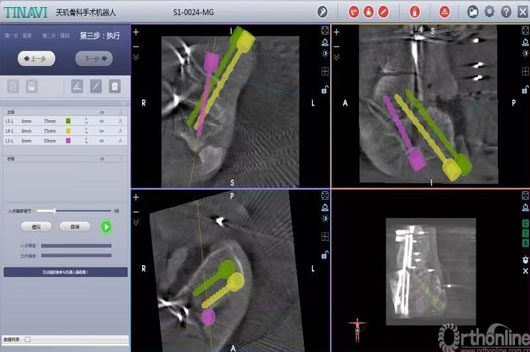

2.jpg

术中妄想螺钉位置